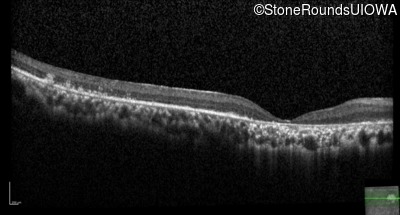

The clinical features supporting the diagnosis of Bardet Biedl syndrome in this patient include: bone-spicule-like pigmentation, narrowed arterioles and macular atrophy on ophthalmoscopy; photoreceptor loss on OCT; ulnar polydactyly, obesity, abnormal cognition, hypertension; and, normally sighted parents.